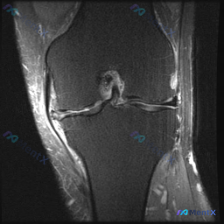

单序列膝关节MRI发现半月板异常,看看这个信号改变符合哪种情况?

看到一份膝关节MRI的影像资料,问题是观察半月板异常,整理一下完整分析思路分享给大家。

这是一份膝关节冠状位T1加权MRI的单影像分析,核心异常聚焦在半月板:

- 骨骼结构:股骨远端、胫骨近端骨质信号均匀,无骨髓水肿、骨质破坏,皮质连续完整

- 关节软骨:关节面软骨形态规整,无明显缺损

- 半月板:

- 外侧半月板:形态正常,无异常高信号,基本正常

- 内侧半月板:体部到髁间窝方向存在明显异常,原本均匀三角形低信号形态消失,可见纵向、斜向异常信号,半月板组织向关节中心移位,形态呈双线/扭曲状

- 韧带:内侧副韧带走行连续,无肿胀或信号异常

- 关节腔滑膜:无明显积液,滑膜无增厚

看到这份影像,第一印象肯定是先抓异常点:只有内侧半月板有明确的信号+形态双重异常,其他结构基本都是好的,这提示病变局限在半月板。

病变局限在内侧半月板,同时存在信号异常和形态移位,其他膝关节结构没有明显异常,这种表现最符合孤立性内侧半月板撕裂,也有可能是在慢性半月板退变基础上发生的急性撕裂。根据移位的表现,还要高度警惕桶柄状撕裂这类可能导致关节交锁的撕裂类型。